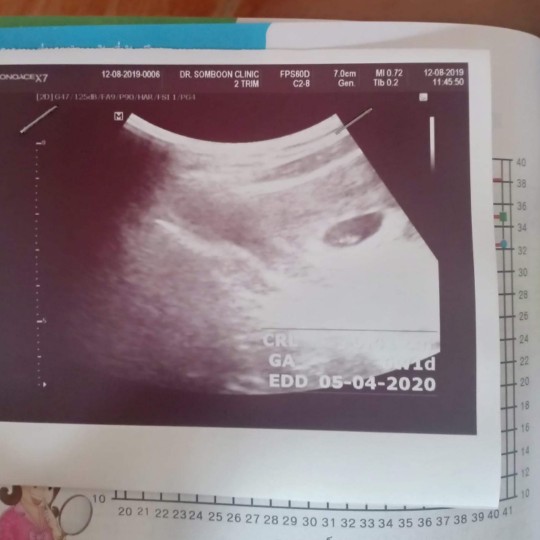

12วีคจ้า